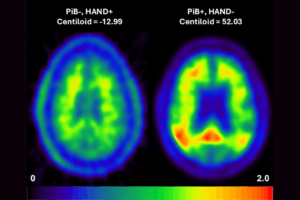

With an increasingly aging global population and no available preventative treatments, Alzheimer’s disease and related dementias are poised to become an even larger public health challenge. The mechanisms underlying Alzheimer’s disease are difficult to study because the disease has a long developmental period during which changes in the brain can occur years before symptoms appear. […]